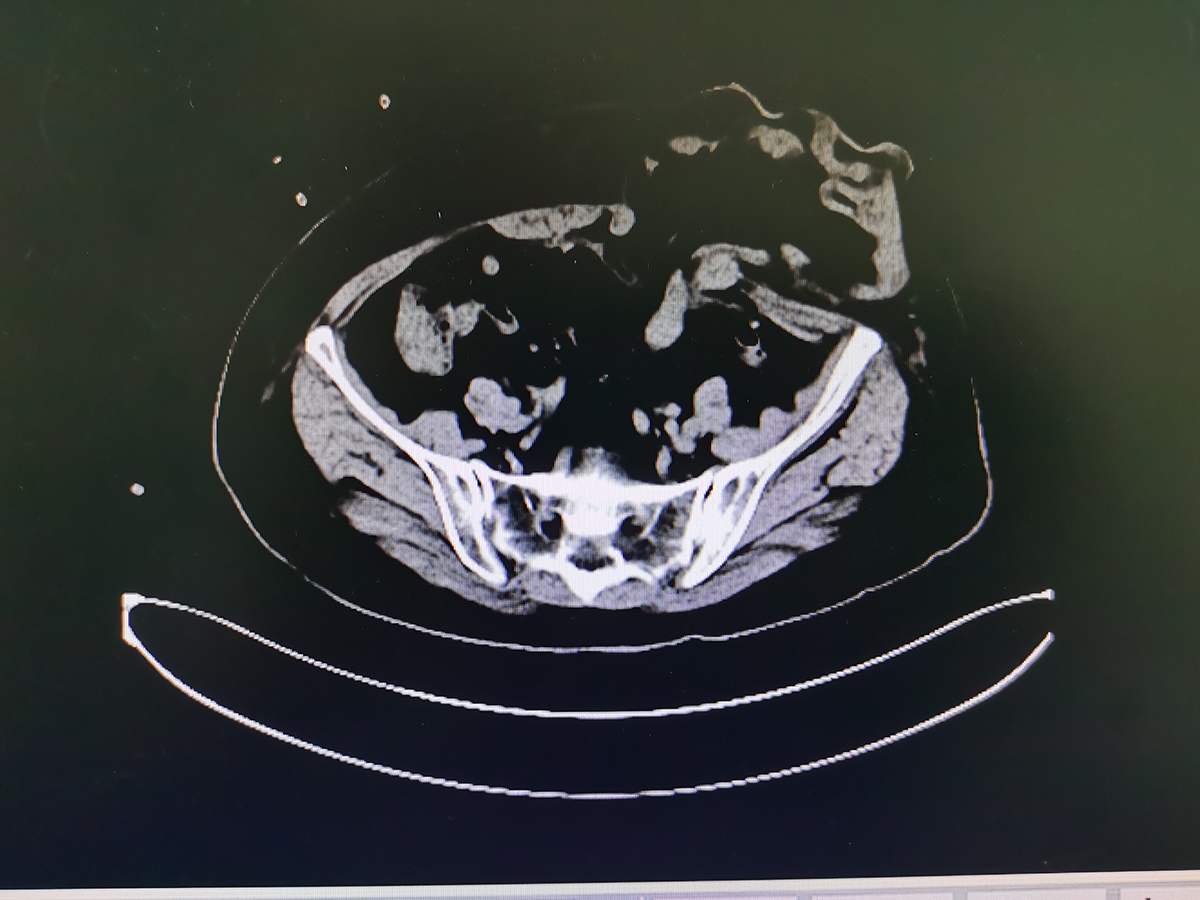

精益求精------造口旁疝联合双侧腹股沟疝修补术

【技术突破】德化县医院完成首例巨大造口旁疝修补术(sugarbaker)

经检查,患者腹壁切口疝长约20厘米,造口旁疝直径约5厘米,且造口护理不